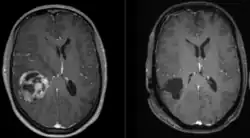

![]() | |

| A coronal view (from the back of the head) of a contrast-enhanced MRI revealing a glioblastoma in a 15-year-old boy | |

When viewed with MRI, glioblastomas often appear as ring-enhancing lesions. The appearance is not specific, however, as other lesions such as abscess, metastasis, tumefactive multiple sclerosis, and other entities may have a similar appearance.[61] Definitive diagnosis of a suspected GBM on CT or MRI requires a stereotactic biopsy or a craniotomy with tumor resection and pathologic confirmation. Because the tumor grade is based upon the most malignant portion of the tumor, biopsy or subtotal tumor resection can result in undergrading of the lesion. Imaging of tumor blood flow using perfusion MRI and measuring tumor metabolite concentration with MR spectroscopy may add diagnostic value to standard MRI in select cases by showing increased relative cerebral blood volume and increased choline peak, respectively, but pathology remains the gold standard for diagnosis and molecular characterization.